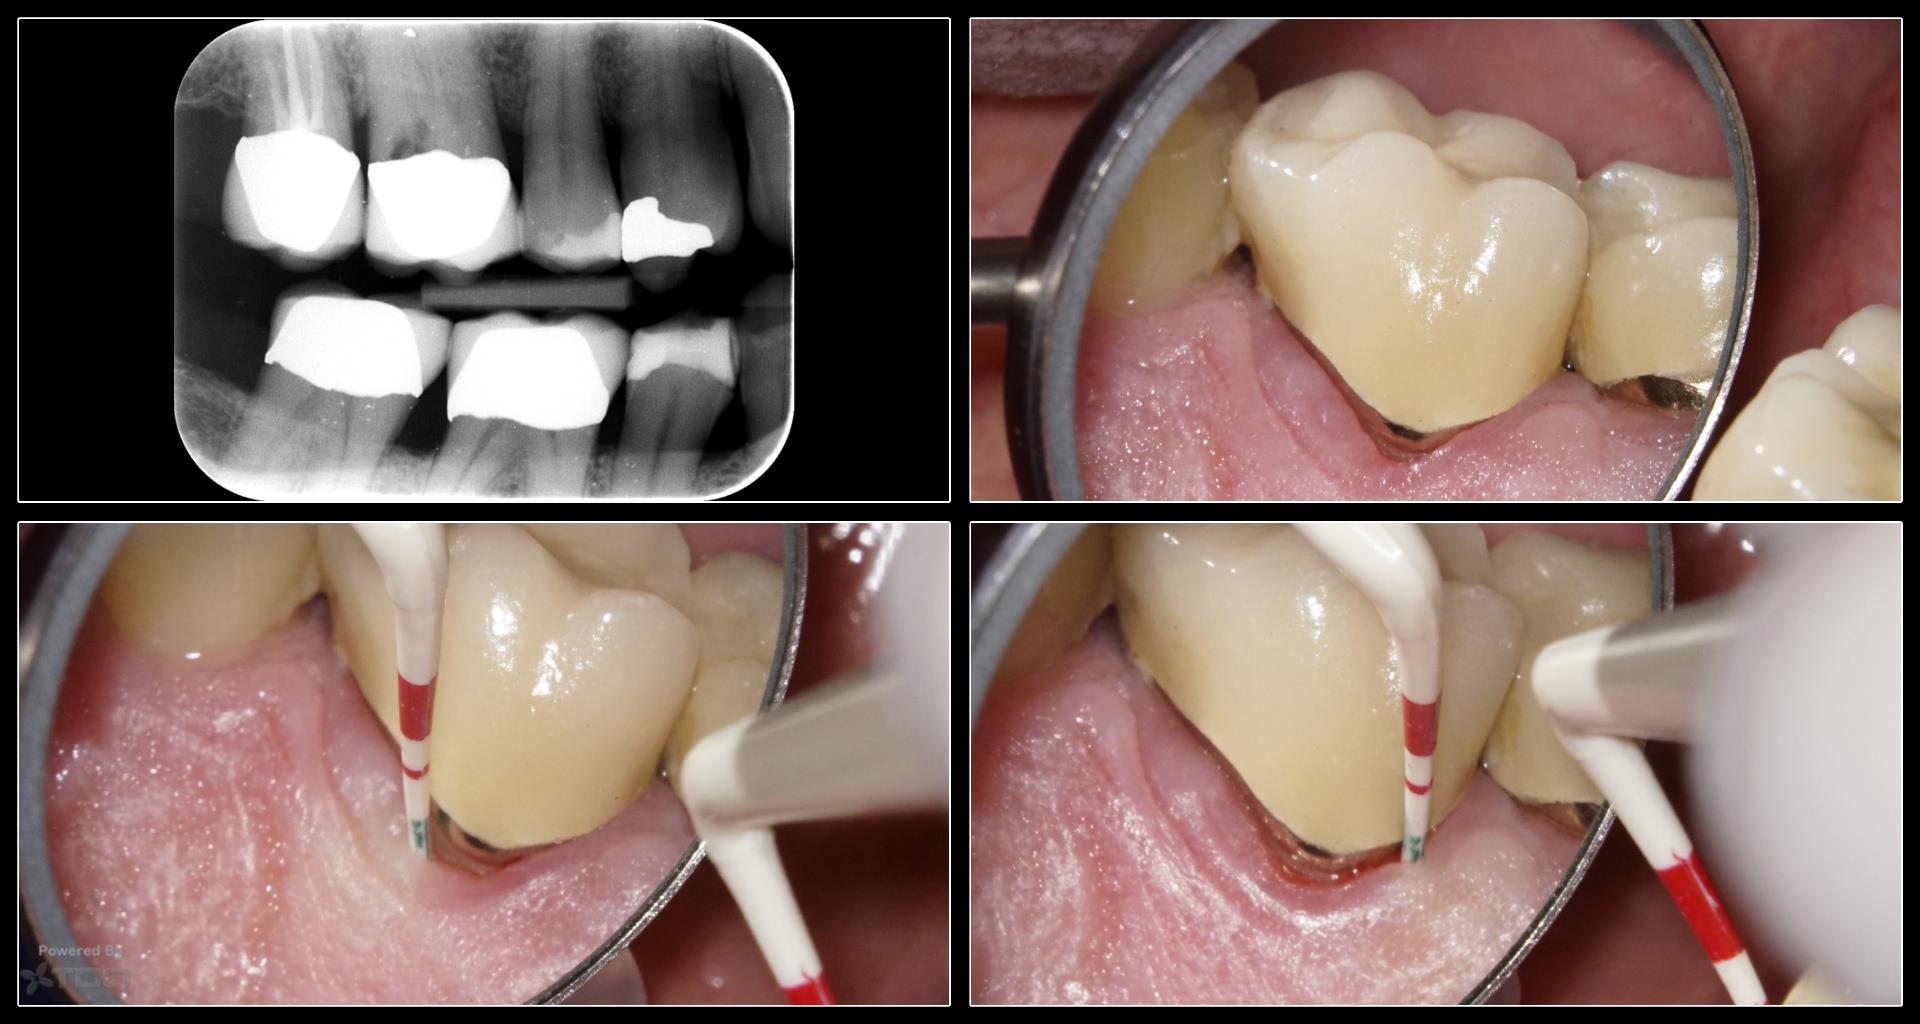

No apparent periodontal communication, treated internally. V-Tapers. Glass fibre post on the palatal canal

Hi Carlos, Thanks for posting. Looks like a very well treated case! However, I’m not sure if the pre-treatment diagnosis was 100% correct as it appears more like internal resorption in the images that you have shown. Pat

Thanks for posting. Looks like a very well treated case! However, I’m not sure if the pre-treatment diagnosis was 100% correct as it appears more like internal resorption in the images that you have shown.